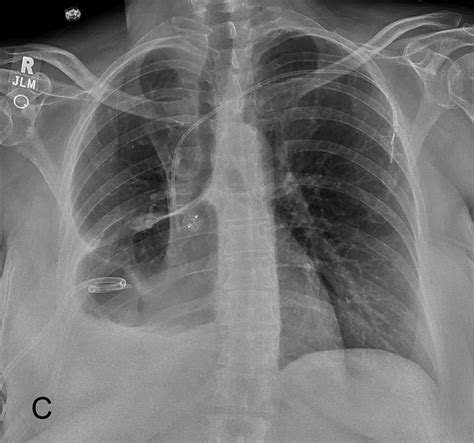

• Chest X-ray: To visualize the pleural space and detect the presence of air or fluid.

Regular chest X-rays or CT scans may be performed to assess the resolution of the pneumothorax and the healing of the lung tissue.